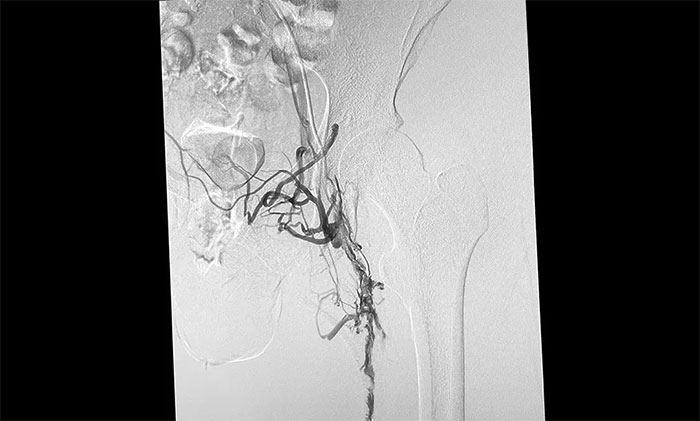

12月15日,席刚明教授在王贵平博士及介入团队协助下顺利行将一个形似伞状的人工滤器经患者右侧股静脉穿刺迅速置入肾静脉下方,“网”住了通往心血管和肺部的致命栓子,阻挡血液栓子进入肺动脉,及时挽救了患者生命。之后对病变血管进行了血栓抽吸术,及接触性溶栓,抽出了大量血栓,复查下肢造影示血栓基本消失,下肢静脉血管再通,整个手术顺利完成。术后,患者下肢肿胀好转。

▲ 下肢深静脉血栓形式